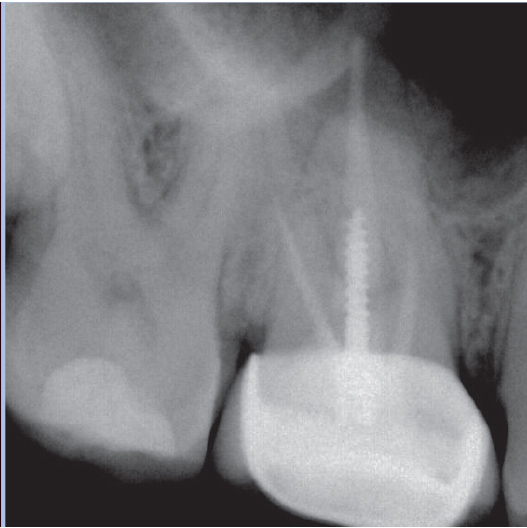

Before

Before Root Canal treatment